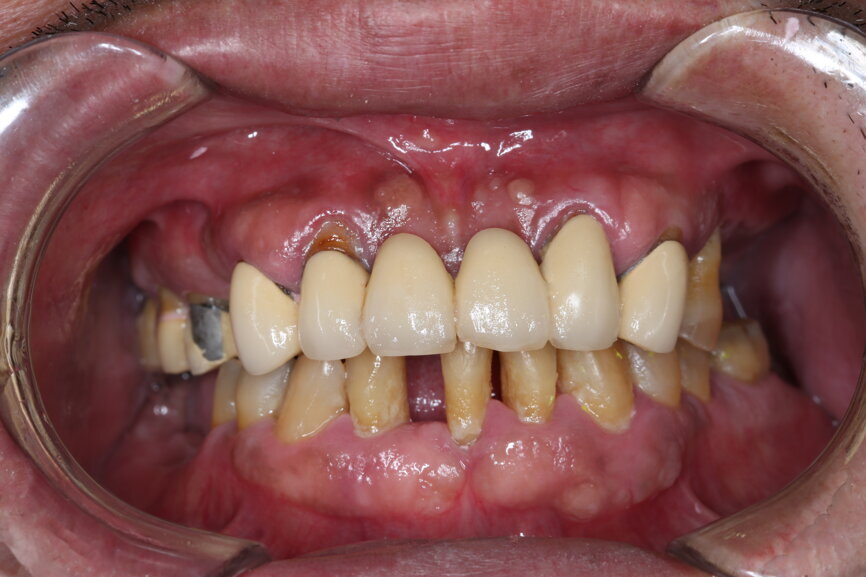

A 51-year-old male patient who was a smoker (< 10 cigarettes per day) and in good general health presented to the clinic with missing molars in the second and fourth quadrants, Grade III mobility of teeth #24 and 17, decayed roots and gingival inflammation, and without abscess or sinusitis of tooth #16. The anterior zone showed  different extents of recession, bone resorption and deep periodontal pockets around teeth #12 and 22, which led to the patient complaining about an aesthetically unsatisfying restoration (Figs. 1 & 2).